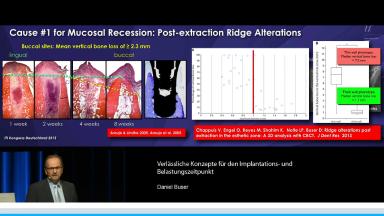

Prof. Buser berichtet in dieser Präsentation, die im Rahmen des Deutschen ITI Kongresses in Dresden im Jahr 2015 gehalten wurde. Langzeiterfolg von Implantaten über 20 Jahre, über den optimalen Implantation und Belastungszeitpunkt. Zunächst erläutert er die gewandelte Altersstruktur der Implantatpatienten und definiert die primären und sekundären Behandlungsziele in der Implantologie. Ein zentraler Aspekt der Präsentation stellt die Wahl des idealen Implantationszeitpunktes nach Extraktion mit Focus auf die verzögerte Sofortimplantation in Verbindung mit GBR dar, die auch mit einem informativen OP Video unterlegt ist. Er setzt sich kritisch mit dem Konzept der Sofortimplantologie auseinander und stellt die Ergebnisse der letzten ITI Konsensuskonferenz dar. Er definiert die Belastungszeitpunkte auf der Basis der ITI Konsensuskonferenz. In einem zweiten Schritt wird die Planung der Belastung in den Zusammenhang mit der Verlaufsbeurteilung der Implantatstabilität mittels ISQ Messung gestellt. Am Beispiel des Sinuslift mit primärer Implantation wird abschließend das Konzept eines flexiblen Belastungszeitpunktes auf Basis der ISQ Messung diskutiert.

- die Wahl des idealen Implantationszeitpunktes in der ästhetisch kritischen Zone verstehen

- die GBR als Technik zur verzögerten Sofortimplantation in der Praxis anwenden können